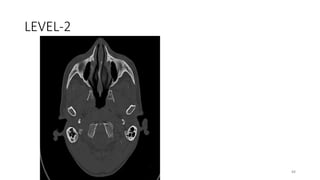

LEVEL-2

88